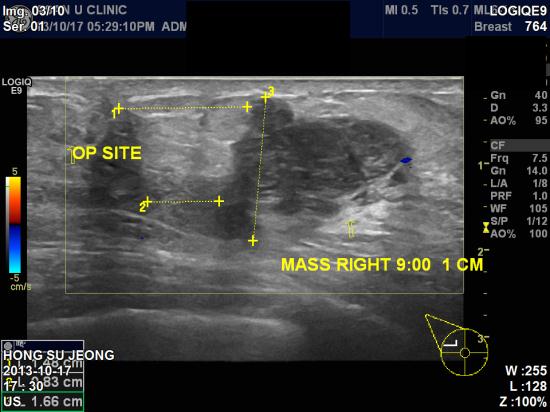

아산유외과 개원 후 27번째 유방암 진단.

1년전

우측유방암 수술받으신분으로 최근 멍우리가 잡혀 검진 후

조직검사 의뢰받고 본원에 내원하신

55

세

여성분이십니다

.

본원에서 시행한 우측유방 조직검사 결과 침윤성 유방암으로

진단되셨습니다

유방암 수술 후에도 합병증과 재발 예방을 위해 정기적인 검진과 관리가

중요합니다